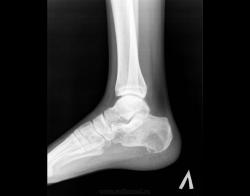

Здравствуйте! Я - молодой доктор, оставшийся один в отделении на целый месяц. Непонятных мне снимков много, вот отдин из них. Женщина 1938г.р., направлена на снимки голеностопного сустава с диагнозом: Артроз. Артроза не вижу, но пяточная кость вызывает подозрения. Что это может быть? Помогите разобраться.

Киста пяточной кости.

+1. Для опыта по-рекомендовал бы сделать аксиальный снимок и томограммы.

На самом деле, я бы в заключение вынесла "кисту" и рекомендовала МРТ